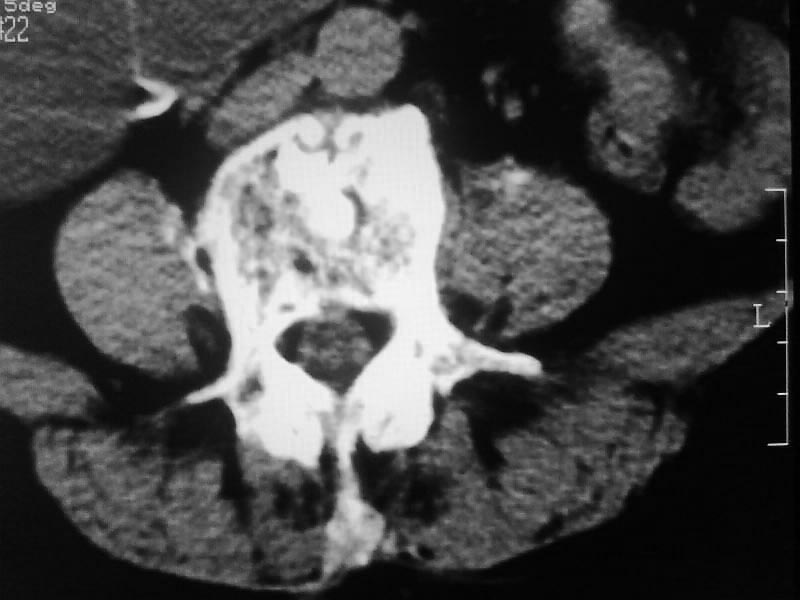

定位相示l2呈楔形改变(ct示陈旧性骨折改变,图像未传),l4.5椎体融合,以下是l4.5ct平扫.请各位看看,

考虑结核(有破坏、硬化及死骨)。

1、三四椎体结核,2、水平骶椎。

1、l1压缩性骨折(陈旧性)。

2、l3、4椎体结核。

就是腰1压缩性骨折,腰3\\4椎体结核(融合),水平骶椎.

支持 l1椎体陈旧性压缩性骨折;l3、4椎体结核(融合);水平骶椎。